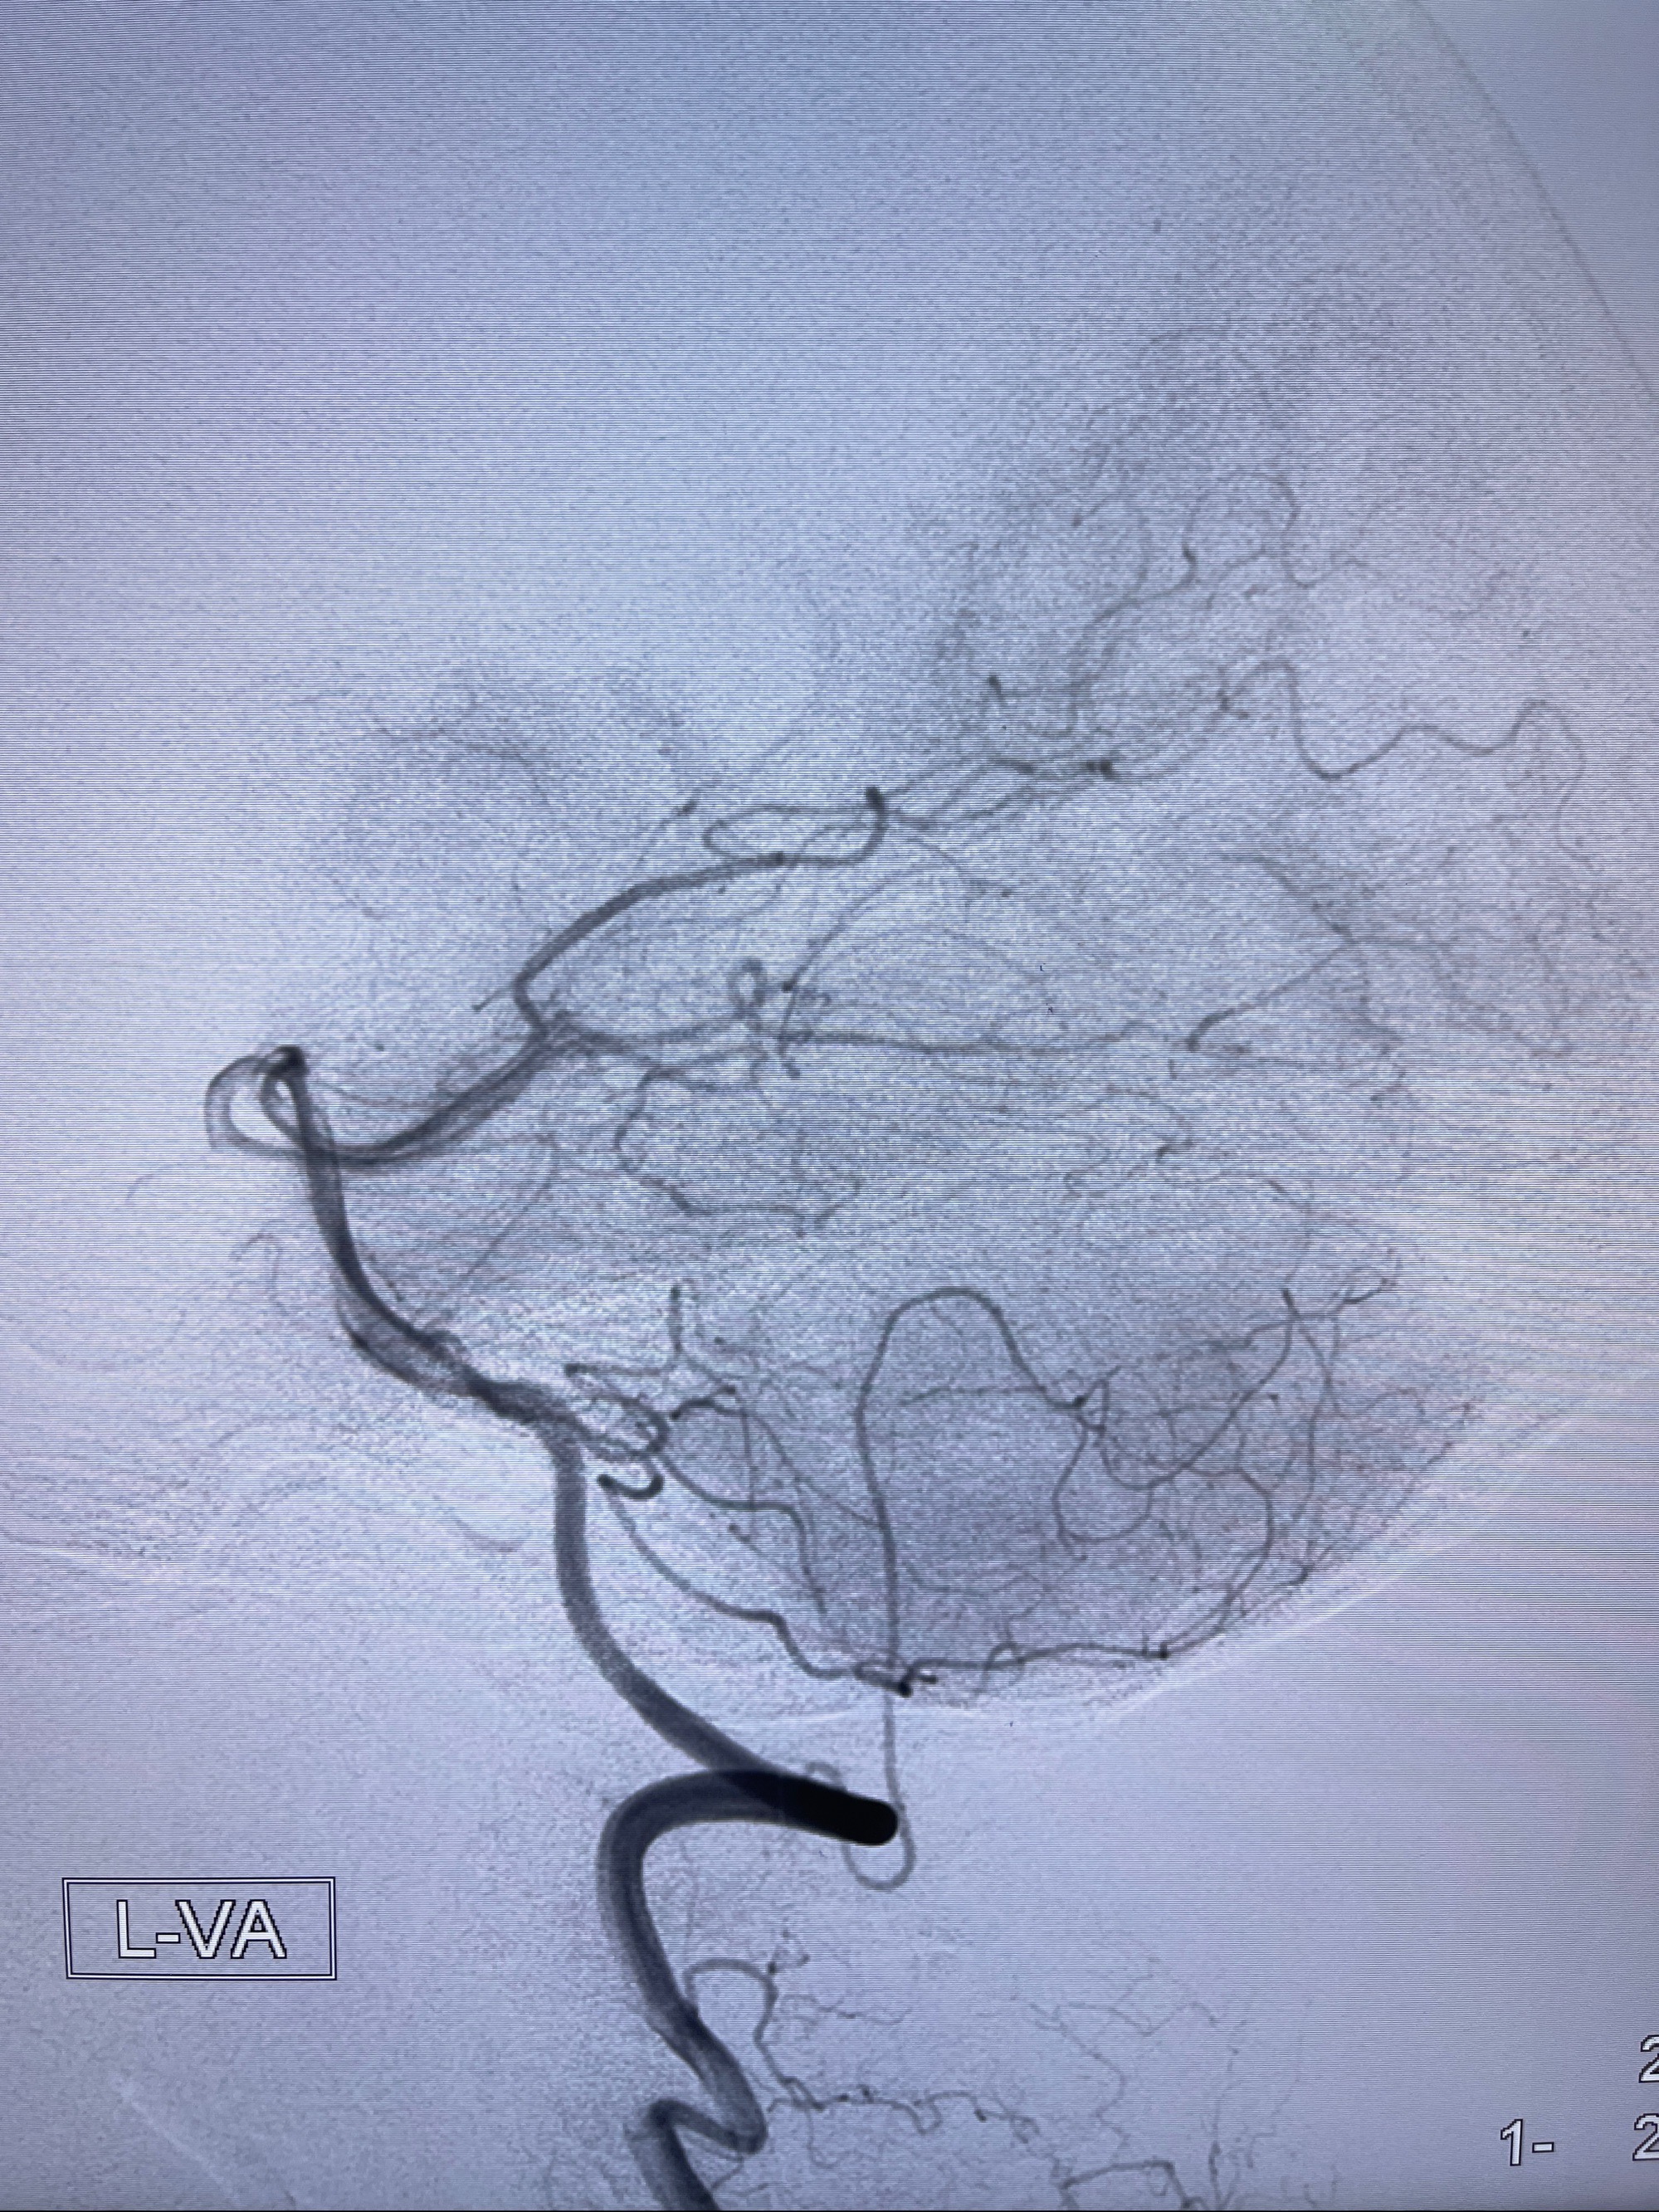

2023-08-30DSA:左侧颈内动脉眼动脉动脉瘤,约3*9.2*7.3mm大小

2023-09-06全麻下行左侧颈眼动脉瘤

密网支架辅助栓塞

麻醉苏醒佳,遵嘱活动!视力视野正常。